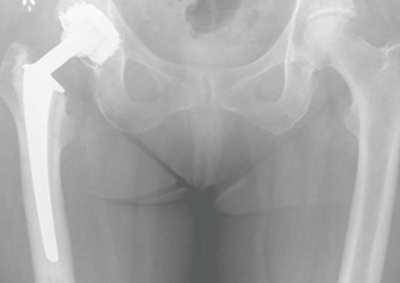

Die SP II Schaftprothese kann bei ausgeprägter Osteoporose mit einer Polyethylenpfanne gekoppelt werden (beidseitig zementiert), bei guter knöcherner Substanz pfannenseitig kann eine zementfreie Pfanne implantiert werden (Hybridprothese).